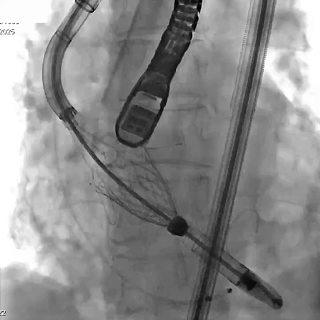

瓣膜释放

瓣膜释放后造影检查瓣膜位置,功能、形态良好,未见明显反流及瓣周漏